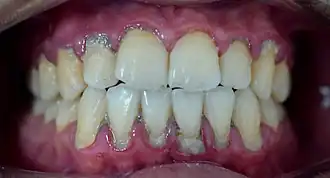

In dentistry, calculus or tartar is a form of hardened dental plaque. It is caused by precipitation of minerals from saliva and gingival crevicular fluid (GCF) in plaque on the teeth. This process of precipitation kills the bacterial cells within dental plaque, but the rough and hardened surface that is formed provides an ideal surface for further plaque formation. This leads to calculus buildup, which compromises the health of the gingiva (gums). Calculus can form both along the gumline, where it is referred to as supragingival ('above the gum'), and within the narrow sulcus that exists between the teeth and the gingiva, where it is referred to as subgingival ('below the gum').

Calculus formation is associated with a number of clinical manifestations, including bad breath, receding gums and chronically inflamed gingiva. Brushing and flossing can remove plaque from which calculus forms; however, once formed, calculus is too hard (firmly attached) to be removed with a toothbrush. Calculus buildup can be removed with ultrasonic tools or dental hand instruments (such as a periodontal scaler).

Supragingival calculus formation is most abundant on the buccal (cheek) surfaces of the maxillary (upper jaw) molars and on the lingual (tongue) surfaces of the mandibular (lower jaw) incisors.[18] These areas experience high salivary flow because of their proximity to the parotid and sublingual salivary glands.